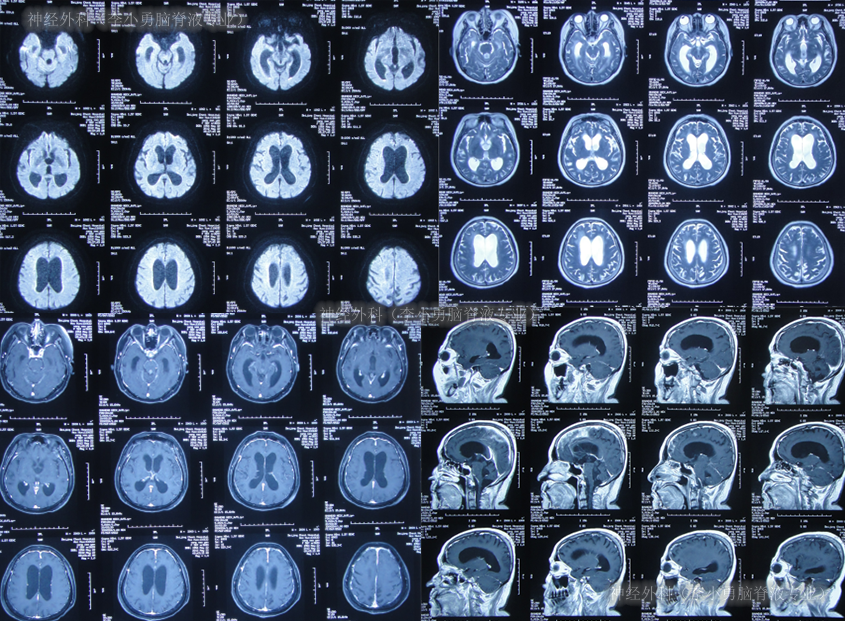

第2家医院出院1月余即2012年2月7日,夜里起夜突然又重复发作以前的症状(恶心呕吐、头昏),且比前2次发作严重,2012年2月8日住入第3家医院:呼和浩特市某三甲医院的神经外科治疗,入院查头颅CT(图-2)和MRI(图-3);脊髓核磁(图-4);肺部CT(图-5)及多次腰椎穿刺脑脊液化验检查(糖低、蛋白高),诊断为:结核性脑膜炎,脑积水。

图-2:2012年2月9日头颅CT